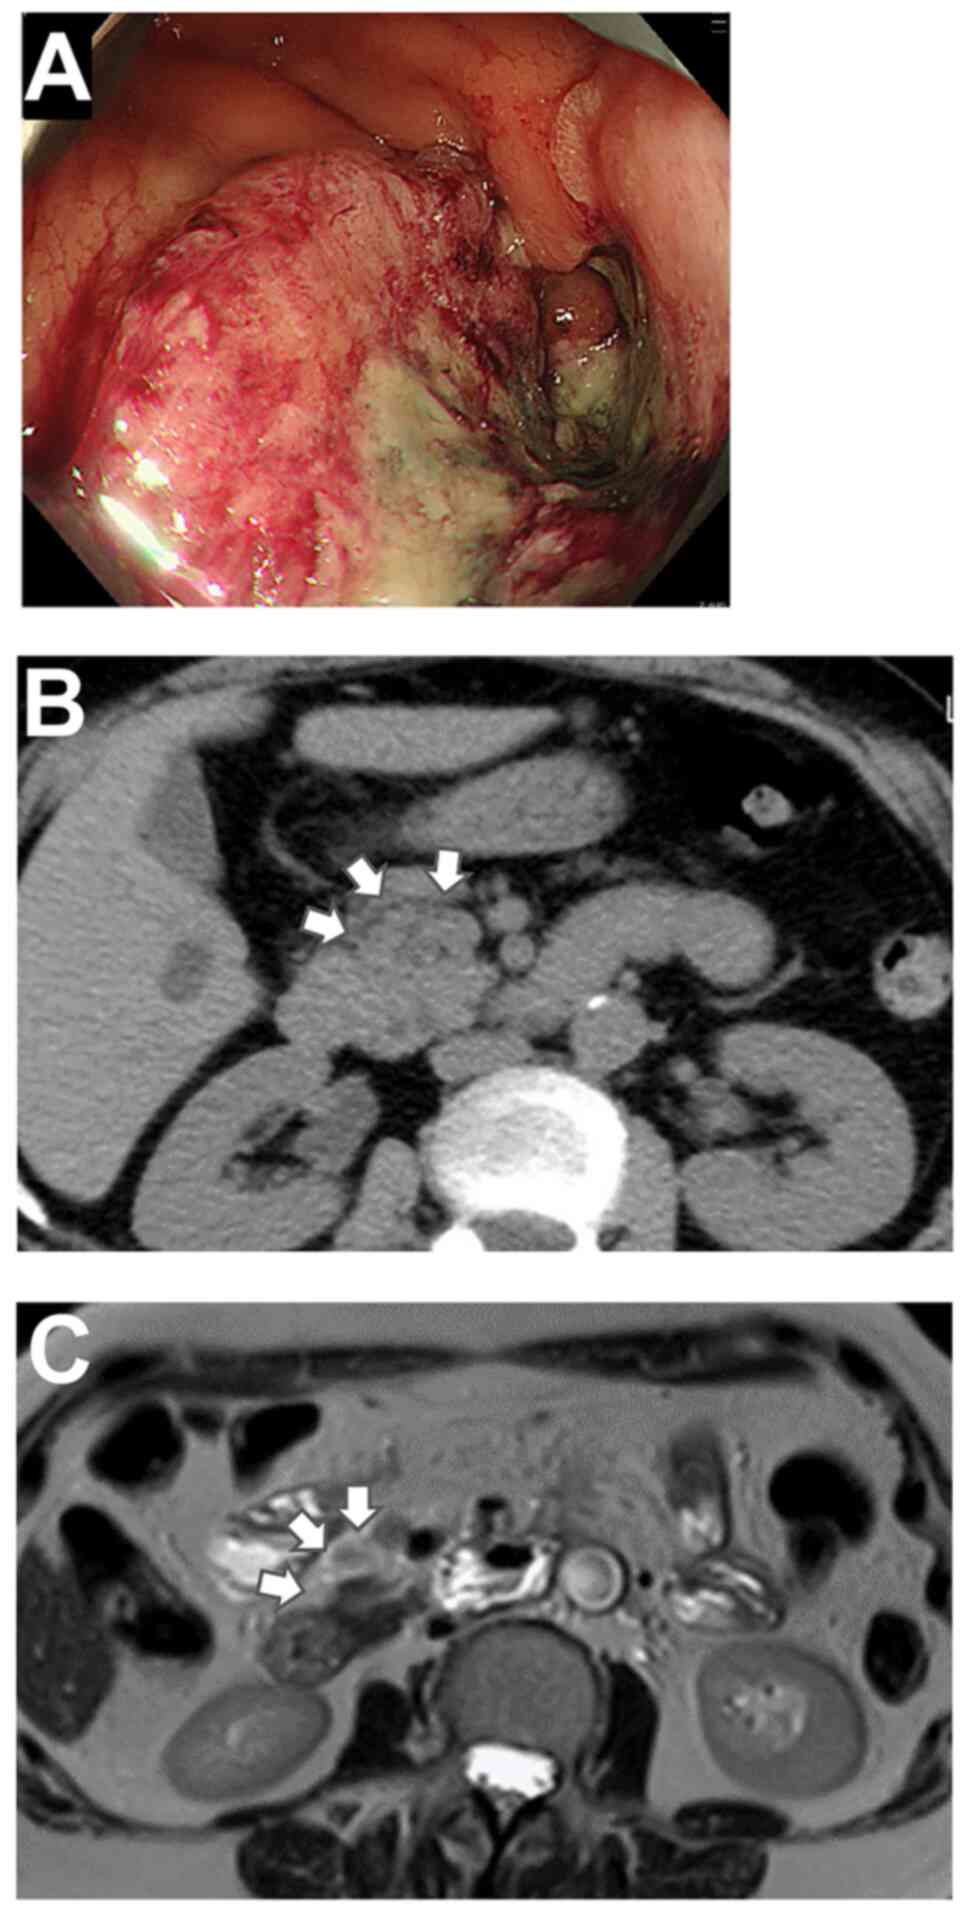

Robotic complete mesocolic excision of right‑sided colon cancer with bulky lymph node metastases using the da Vinci® Si™ system: A case report

Reports on robotic surgery in the treatment of right‑sided colorectal cancer most commonly use the da Vinci® Xi™ system; however, with the increasing popularity of robotic surgery for the treatment of colon cancer, it is likely to be performed using the da Vinci Si™ and X™ systems. The present study reported the case of a 63‑year‑old woman who underwent complete mesocolic excision (CME) with the da Vinci Si system involving a rotation technique for ascending colon cancer with bulky lymph node metastasis to the anterior pancreas. Robot‑assisted right hemicolectomy was planned for this patient with T4aN2bM0, stage IIIc cancer. A lap protector and EZ access (Hakko Co. Ltd.) were fixed in the umbilical incision, and the da Vinci camera port was placed just off‑center at the EZ access to allow the camera port to be repositioned by rotating it. The medial approach was used. The bulky metastatic lymph nodes at the head of the pancreas were dissected after ligating the right colic artery and vein. During CME, rotation of the EZ access was used to avoid interference between the robotic arms. The right colon was released from the retroperitoneum and resected. A functional end‑to‑end anastomosis was created, and right colectomy was successfully completed. The total operation time was 271 min and the console time with the da Vinci Si system was 140 min. The patient was discharged on postoperative day 8 without complications. In conclusion, robotic right colectomy was successfully performed and rotation of the EZ access facilitated robotic surgery using the da Vinci Si system.

Figure 1

Figure 2

Figure 3